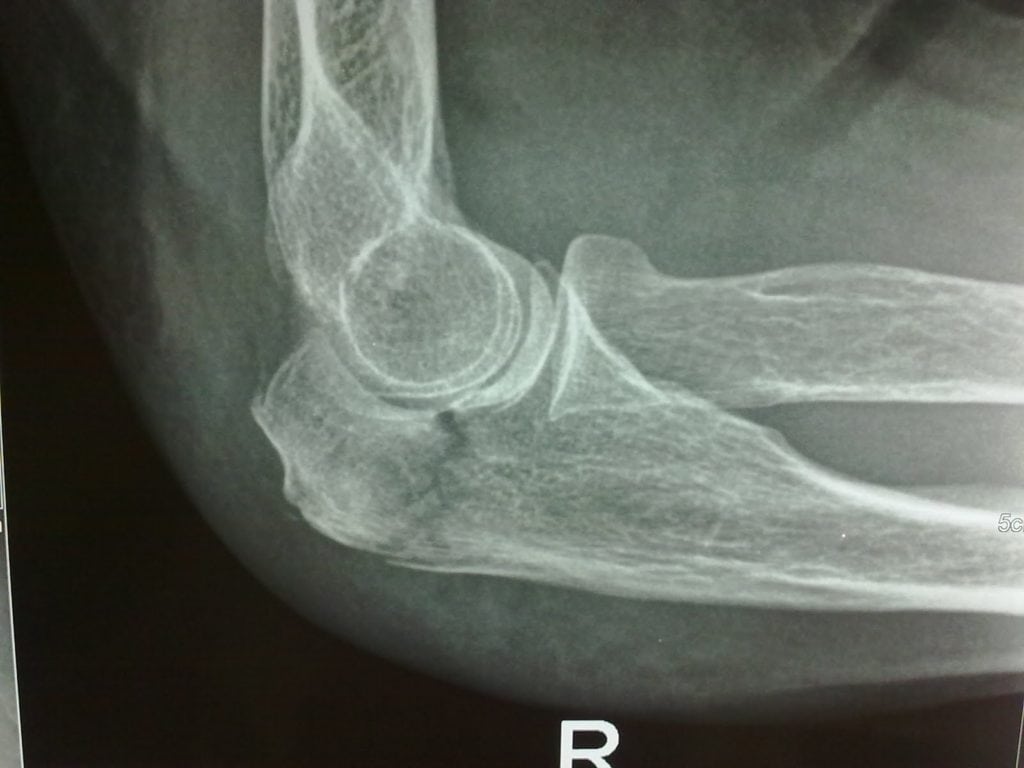

При переломах образующих его костей происходит ограничение функций всей руки. Возникают препятствия при попытке выполнить любое элементарное движение, например, развернуть кисть вверх. Полное восстановление функций локтя возможно только при размещении костей и их отломков в анатомическом положении, обеспечивая их быстрое сращение. Ведущий метод диагностики всех переломов локтевого сустава — рентгенография. Метод лечения зависит от локализации и тяжести травмы, возраста пациента. Если консервативное лечение (наложение гипса) не окажет эффекта, больного готовят к хирургической операции.

- травмы чрезмыщелковые, межмыщелковые. Это самые часто диагностируемые виды переломов, обычно возникающие при сильном ударе в локоть. Поддерживающие надмыщелки костные структуры разрушаются, что становится причиной изменения соотношения костей. Для таких травм характерно серьезное повреждение хрящевых тканей, восстановление которых является сложной задачей. После репозиции суставных элементов они крепятся винтами и пластинами до полного их сращения. Это не станет ограничением для постепенной разработки сустава.

Во время диагностирования оценивается состояние кровеносных сосудов, степень кровоизлияния в суставы. При проведении операции хирургу приходится восстанавливать и поврежденные нервы. Если этим этапом пренебречь, то разовьются тяжелейшие осложнения. Нарушение иннервации спровоцирует потерю чувствительности кисти, также возможно значительное снижение объема движений в локте.